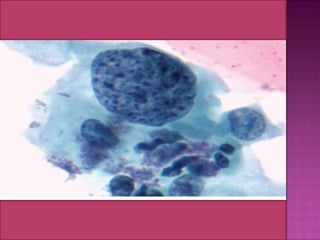

ballooned cytoplasm  koilocytes from the

Greek word for ‘‘empty space,’’

 similarity to descriptions of Reagan’s mild

dysplasia.

 In 1976, Meisels and Fortin linked

koilocytotic atypia with HPV.